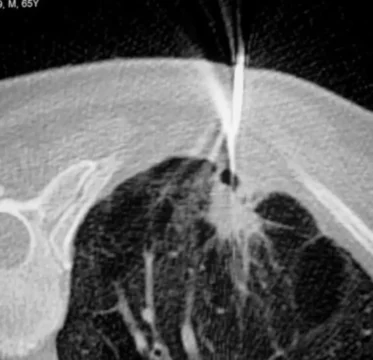

Endoscopie respiratoire diagnostique et interventionnelle

Médecins

Dr J. Boutros

Dr J. Benzaquen

Pr C. Marquette